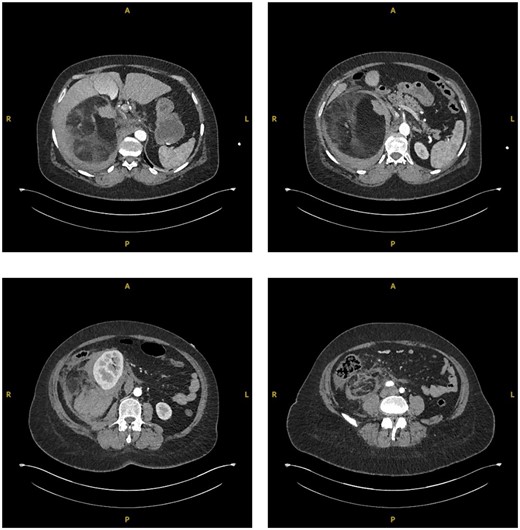

The patient was subsequently transferred over to the local specialty Urology Centre. Here the patient became tachycardic and required supplemental oxygen. A suspicion of increasing blood loss or a pulmonary embolism (PE) was raised. A repeat CTAP in arterial and venous phases along with a CT pulmonary angiography (CTPA) was conducted. The CTAP again showed a large right-sided retroperitoneal mass, now described as mixed fat and soft tissue densities characteristic of AML. The surrounding retroperitoneal bleeding was thought to have increased in size, indicating likely active haemorrhage (Fig. 2). CTPA showed no PE.

Sequential transverse sections of CTAP in arterial phase showing extent of lesion down to level of right Ilium bone.